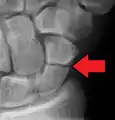

A subtle scaphoid fracture

A more obvious scaphoid fracture on a scaphoid view X ray

Radiolucency around a 12 days old scaphoid fracture that was initially barely visible.[12]